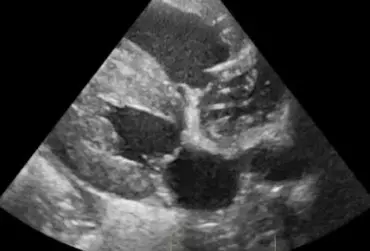

Zarażenie psa pasożytem nicieniem Dirofilaria immitis – opis przypadku

W artykule opisano przypadek dirofilariozy u psa wywołanej D. immitis. U badanego pacjenta stwierdzono patognomiczny obraz zmian w badaniu rentgenowskim i ultrasonograficznym układu sercowo-naczyniowego.